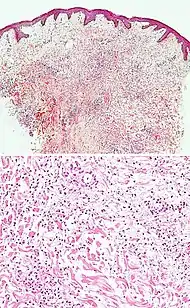

Lupus erythematosis Typical findings in systemic lupus erythematosus:[8]

• Fibrinoid necrosis at the dermoepidermal junction

• Liquefactive degeneration and atrophy of the epidermis

• Mucin deposition in the reticular dermis

• Edema, small hemorrhages

• Mild and mainly lymphocytic infiltrate in the upper dermis

• Fibrinoid material in the dermis around capillary blood vessels, on collagen and in the interstitium

• In non-bullous cases, perivascular and interstitial neutrophils are sometimes present in the upper dermis, with damage to blood vessels